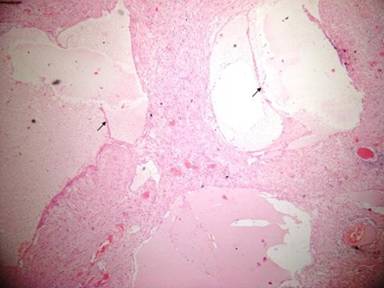

Histopathological examination showed large septate lymphatic channels in a background of connective tissue stroma. The tumor contained serous fluid. The stroma had multiple cholesterol crystals, lymphocytes, smooth muscles and congested thin walled vessels. The lymph nodes showed reactive changes. The final histological diagnosis was of cystic lymphangioma of the pancreas (Figures 5 and 6). The surrounding pancreas parenchyma was unremarkable. The patient is doing well 12 months postoperatively.

Figure 6. Hematoxylin and eosin (x100) staining shows dilated lymphatic channels of varying sizes, separated by thin septa (black arrows). The cystic spaces are lined with flattened or cuboidal endothelial cells. |